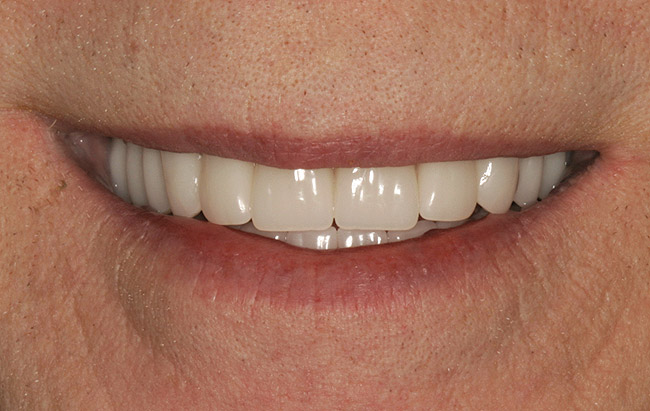

In overdenture therapy, prosthetic design can be divided into two groups: stress-broken and rigid. Stress-broken prostheses require fewer implants, with attention to biomechanical design features to allow for rotation (stress-breaking) of the prostheses around the implant locations. These prostheses are essentially tissue-supported and implant-retained. They replace the adhesive/glue, providing needed retention, comfort, and support. An example would include two implants in site Nos. 23 and 26, with either solitary anchor systems (ball or stud attachments) or a splinted bar-overdenture design (Figure 9 through Figure 11). Masticatory function is improved and patient satisfaction increased. Rigid prostheses require multiple implants, with the forces being transferred from the supra-infrastructure directly to the implants. These prostheses are implant-supported and implant-retained. The design can be removable or fixed (Figure 12 through Figure 16), depending on patient- and operator-mediated preferences.24-27 Within the fixed group of prostheses, materials used may vary from acrylic-fused-to-metal, porcelain-fused-to-metal, or all-ceramic. The cost of these material choices varies significantly, with acrylic options providing the most affordable, entry-level approach for the patient.14